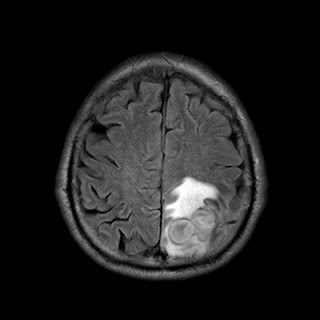

Caso neurorradiología

Paciente de 60 años con cuadro de 1 semana de evolución consistente en tropiezos frecuentes y alteración en la movilidad del miembro

inferior derecho. No refiere

cefalea u otros síntomas asociados, no pérdida de peso, no náuseas o emesis, no

sudoración nocturna. Antecedentes de hipertensión arterial y diabetes.

Resonancia magnética